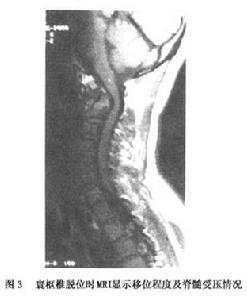

(2)CT及MRI檢查:普通CT、CT三維重建和矢狀面MRI檢查將有助於對這種損傷的診斷,以及對脊髓受累情況的判定。

2.CT及MRI檢查 普通CT、CT三維重建和矢狀面MRI檢查將有助於對這種損傷的診斷,以及對脊髓受累情況的判定。